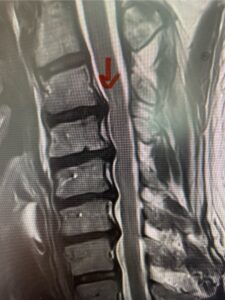

This 61-year-old female with a history of severe osteoporosis and a prior history of a laminectomy from l2-S1 with an L5-S1 instrumented fusion, presents with progressive low back pain and right lower extremity radiculopathy. MRI revealed a grade 1 L2-3 spondylolisthesis with severe stenosis mainly from severe right L2-3 facet joint hypertrophy which was compressing the right L3 descending nerve root. (Fig. 1). She had failed conservative management consisting of physical therapy and pain management with epidurals. She underwent an L1-3 revision laminectomy where we had to dissect a plane underneath the inferior aspect of the L2 lamina. We performed an instrumented fusion at L2-3 with special hydroxyapatite-coated screws to improve fixation to surrounding bone given here severe osteoporosis (Fig. 2) This worked out well and the patient had an uneventful recovery with relief of her leg pain.

Figures 1a: Sagittal and axial T2-weighted lumbar MRIs demonstrating a grade 1 L2-3 spondylolisthesis (red arrow) with severe stenosis secondary to right L2-3 facet hypertrophy (red arrow).

Fig 1b: Note the left L2-3 facet joint (blue arrow) is normal in size compared to the right (red arrow)